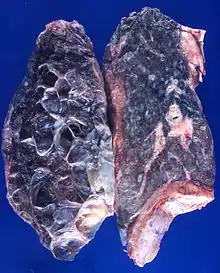

| Left lung completely affected by bullae shown in contrast to a normal lung on the right. | |

In the lungs, emphysema involves enlargement of the distal airspaces,[2] and is a major feature of chronic obstructive pulmonary disease (COPD). Other pneumatoses in the lungs are focal (localized) blebs and bullae, pulmonary cysts and cavities.